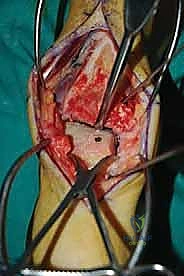

تصبح هذه الآفات أكثر تعقيداً وخطورة عندما تُصنف على أنها "كبيرة الحجم" (عادة يكون قطرها أكبر من 1.5 سم أو مساحتها تزيد عن 1.5 سم مربع، أو تكون عميقة جداً). هذه الآفات الكبيرة غالباً ما تشمل منطقة حرجة تُعرف باسم "كتف الكاحل" (Talar Shoulder) - وهي منطقة الانتقال التشريحية الحساسة حيث يلتقي غضروف القبة العلوية الأفقي مع غضروف الكاحل الإنسي (الداخلي) أو الجانبي (الخارجي) العمودي.

كثيراً ما ترتبط هذه الآفات الكبيرة بوجود تكيسات عظمية ضخمة تحت الغضروف، مما يترك الغضروف المتبقي بدون أي دعم هيكلي، فينهار كما ينهار السقف الذي سقطت أعمدته. هذه الآفات، على الرغم من ندرتها مقارنة بالإصابات البسيطة، يمكن أن تؤثر بشكل خطير ومأساوي على وظيفة الكاحل، وتؤدي حتماً إلى التهاب مفصلي تنكسي متقدم (Osteoarthritis) في سن مبكرة إذا تركت دون العلاج الجراحي السليم الذي يقدمه الأستاذ الدكتور محمد هطيف.

الغوص العميق في جراحة الطعم الخيفي الهيكلي (Structural Allograft Reconstruction)

يهدف هذا الإجراء العبقري إلى استبدال الغضروف والعظم التالفين والميتين بنسيج سليم تماماً مأخوذ من متبرع متوفى (طعم خيفي - Allograft). هذا الطعم يتم تعقيمه وحفظه في بنوك الأنسجة العالمية وفقاً لأعلى المعايير الطبية الصارمة لضمان خلوه من أي أمراض معدية والحفاظ على حيوية الخلايا الغضروفية.